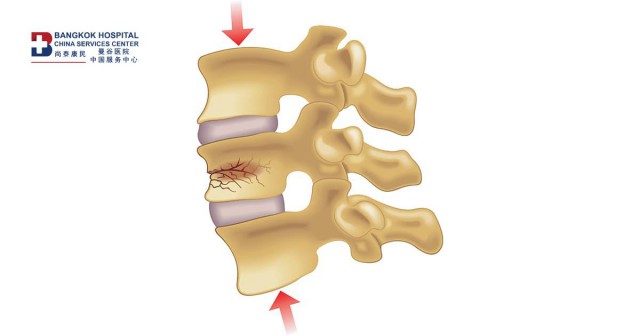

脊柱凹陷原因

曼谷医院脊柱中心Chaidej Srasomboon博士指出,骨质疏松症导致的脊柱凹陷是老年人的常见问题,尤其是女性,主要原因是骨质疏松引起的椎骨脆弱,导致骨组织容易断裂。

骨质疏松症引起的脊柱凹陷最常发生在60岁以上的老年人身上,通常有意外跌倒或臀部磕碰的病史。

曼谷医院脊柱中心Chaidej Srasomboon博士指出,椎间盘凹陷通常发生在下胸椎和上腰椎之间的交界处(Thoracolumbar Junction) ,患者通常有上腰椎区的背痛,在大多数情况下,骨质疏松症引起的椎体凹陷不会导致神经受压,这将导致患者只有背部疼痛。但在某些患者中,可能会压迫神经,它会导致腿部疼痛、腿部麻木、无力以及排尿或排便困难。